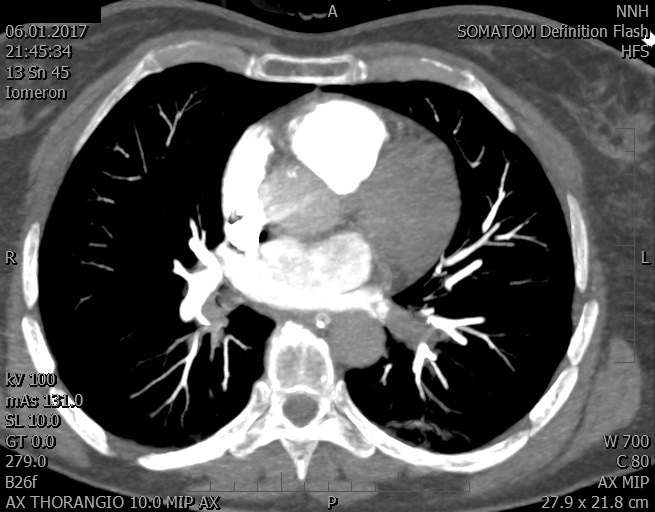

Video 2 - Echokardiograficky byla zjištěna těžká dysfunkce dilatační levé komory s nezvětšenou pravou komorou.Pro nejasnou příčinu zástavy jsme provedli i vyšetření výpočetní tomografií (CT), které vyloučilo plicní embolizaci (série 1 - soubory na konci článku). V den přijetí při přetrvávající oběhové nestabilitě byla nemocná opakovaně defibrilována pro fibrilaci komor se stabilizací rytmu po podání amiodaronu a mesocainu. Dle hemodynamických měření se jednalo o těžký kombinovaný šok. Vstupní laboratorní vyšetření bylo bez větších pozoruhodností. Posléze jsme doplnili anamnézu od příbuzných a zjistili, že pacientka užila do dvou hodin před srdeční zástavou první tabletu amoxicilinu na lehký respirační infekt. Při nevýtěžnosti vstupních vyšetření a nových anamnestických informacích jsme doplnili 14 hodin po kolapsu vyšetření koncentrace tryptázy v séru, která byla extrémně zvýšena (tabulka 2), což nás vedlo k podezření na anafylaxi.